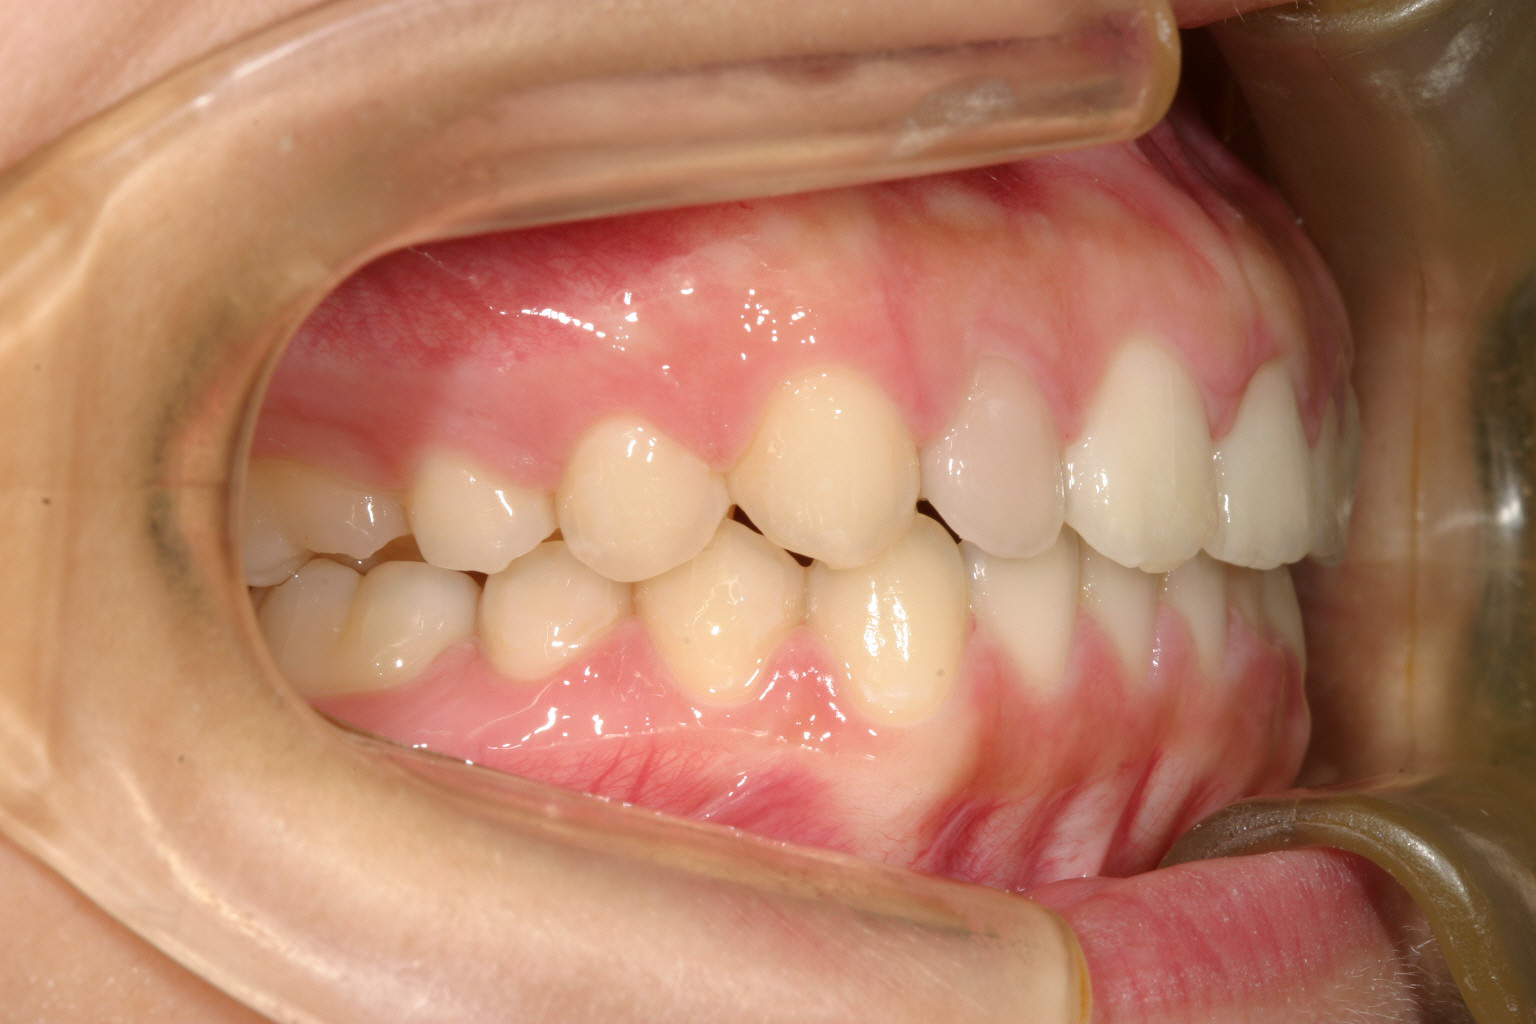

横なら見ると少し出っ歯が気になります。

前突感も無くなり最高のオーバージェットです。

この様な隙間を閉じる症例はインビザラインにとって一番得意とする症例です。

出っ歯もIPRと言ってワザと隙間がなければ歯と歯の間に削る事により隙間を作って全体的に締め付ければいいだけですから、マウスピースタイプの矯正装置にとって最高の症例となります。